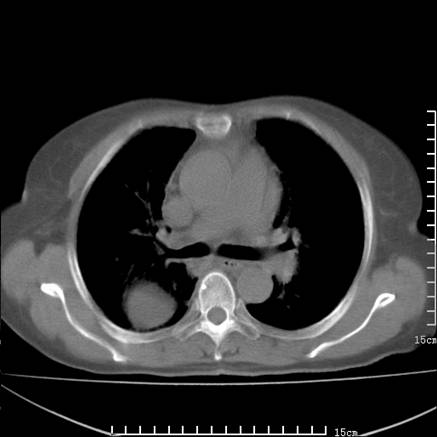

女,王某,58岁,咳嗽三个月余,基层医院二个月前诊为肺结核,用抗结核药二个月无明显疗效。

心包积液致肺瘀血.右侧周围型肺癌伴肺内转移,中间裂积液,叶间胸膜肥厚.右上肺大泡,右侧胸膜肥厚.

双肺继发型tb,心功能不全并肺淤血、心包、双侧叶间裂积液,肺大泡,右下胸膜肥厚钙化。

支持  双肺继发型tb,心功能不全并肺淤血、心包、双侧叶间裂积液,肺大泡,右下胸膜肥厚钙化。